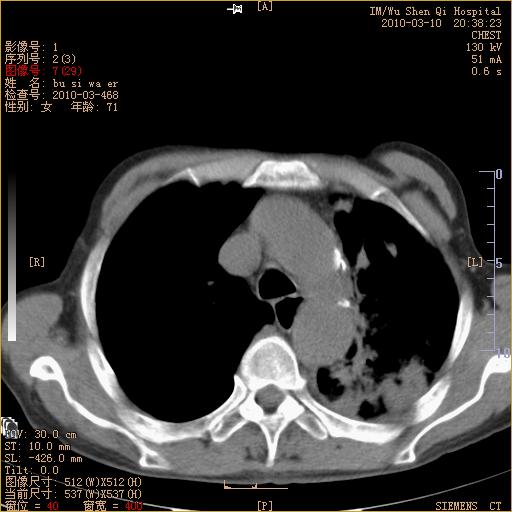

以下是引用随光逐影在2010-3-11 0:41:00的发言:[br]1)考虑左肺及右肺上叶继发性肺结核并左肺炎症感染。2)左侧支气管内膜结核可能;建议必要时行纤支镜检查。3)肺气肿。4)心包膜增厚(或少量心包积液)。5)左侧胸腔积液。